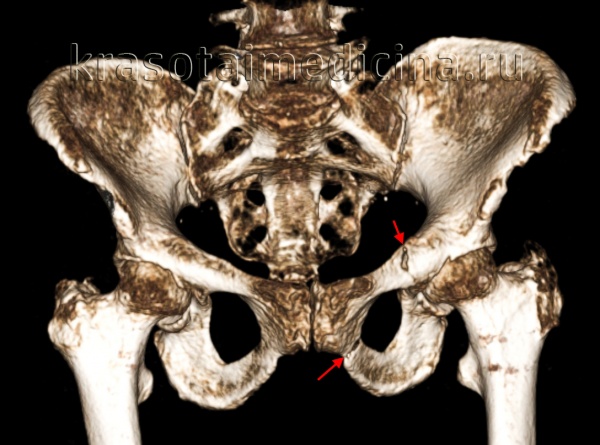

(Справа) КТ, аксиальный срез: у этот же пациента определяется диффузное расширение левого КПС, указывающее на полный разрыв передних и задних связок левого крестцово-подвздошного сочленения. Правое крестцово-подвздошное сочленение расширено только спереди. (Слева) КТ, 3D реконструкция: у женщины 75 лет определяются переломы по типу ЛК I. Отмечаются косые переломы ветви лобковой кости слева и вколоченный перелом 2 зоны крестца слева.

(Справа) КТ, 3D реконструкция: у мужчины 50 лет определяется травма по типу ПЗК II. Лобковый симфиз расширен >2,5 см. Левое крестцово-подвздошное сочленение расширено спереди, но сзади нормальное. Задние крестцово-подвздошные/ сочленения/связки также должны быть оценены на других проекциях, поскольку при разрыве формируется нестабильная травма по типу ПЗК III.

(Слева) КТ, сагиттальный срез: у пациента определяется травма по типу вертикальной трещины. В данном типе травмы также нередки поперечные переломы крестца, которые обычно визуализируются на сагиттальных изображениях. Также отмечается перелом позвонка на уровне S1.

(Справа) КТ, аксиальный срез: определяется травма по типу ПЗК III, повязка на таз, уменьшающая изначальную боковую ротацию левой тазовой кости. Также определяются двусторонние переломы крестца. (Слева) КТ-артериография, 3D реконструкция: определяется травма по типу ПЗК III (после прикрепления повязки) с переломом ветви лобковой кости, перелом вертлужной впадины слева, разрыв правого крестцового-подвздошного сочленения и перелом крыла крестца во второй зоне справа. Этот тип травмы обладает высокой ассоциацией с повреждениями артерий.

(Справа) Рентгенография в передне-задней проекции: у этого же пациента после наружной фиксации спереди и фиксацией КПС винтами определяется постоянное смещение правого крестцово-подвздошного сочленения. На повторной КТ определяется костный осколок, препятствующий репозиции. (Слева) КТ с контрастированием, выполненная после размещения тазовой повязки по поводу травмы по типу ПЗК, коронарный срез: определяется мочевой пузырь, смещенный кверху из-за гематомы. Также отмечается травма простатического отдела уретры с экстравазацией контраста.